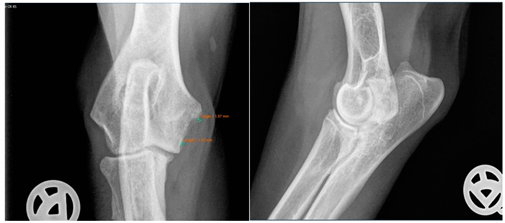

Moreover, Trochlear Notch Sclerosis (TNS), a radiological term denoting increased bone radio-opacity in the ulnar trochlear notch region, was quantified. The measurements adhered to the methodology outlined by Draffan et al. [

13], and the comprehensive TNS ratio of sclerosis to the ulnar depth was subsequently computed (

Figure 1). All measurements were performed by the first author of the article.